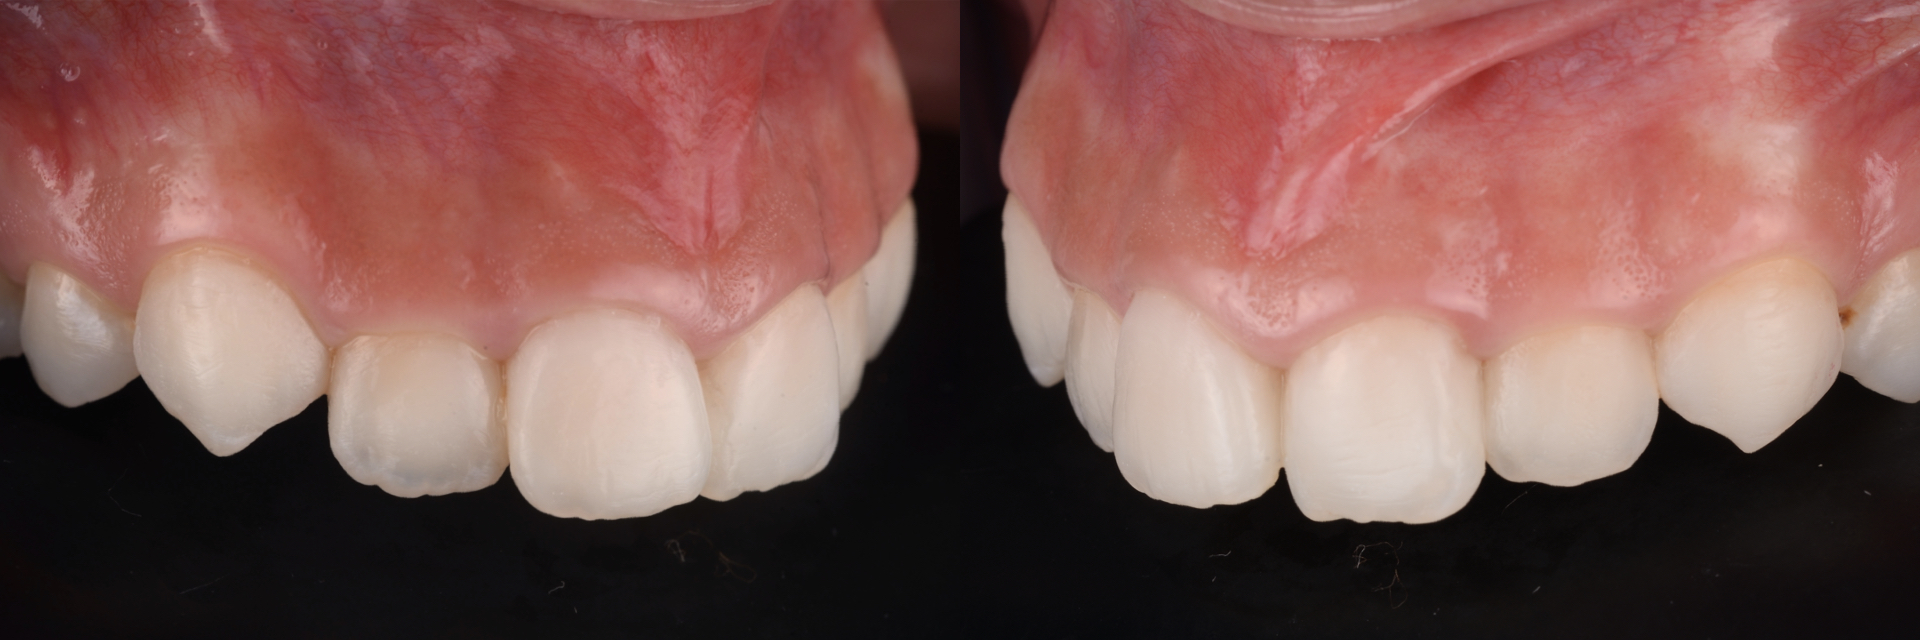

治療前

治療後